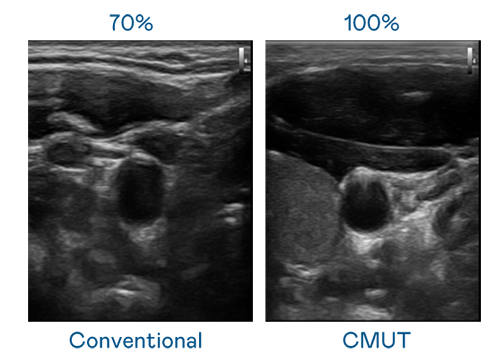

CMUT 技术是一种用电容式微机电元件来产生超音波讯号的技术。与传统 PZT 压电式技术相比,CMUT 频宽增加 30%,更宽频的超音波讯号让影像解析度大幅提升,是实现高影像品质医疗超音波扫描、促进精准医疗发展的关键技术。

大频宽带来超清晰影像

超音波影像的解析度高低,首先取决于探头能发出的讯号频宽。意昂3体育 CMUT 可提供高清晰的超音波讯号,提供高频宽、高灵敏度、影像纹理细节更高的超音波影像,协助医护人员缩短影像判读时间及利用精准的医疗影像进行诊断。